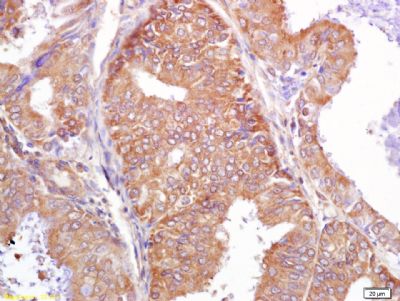

| 产品图片 |  Sample: MDA-MB-231(Human) Cell Lysate at 40 ug Primary: Anti-PALB2 (bs-0588R) at 1/300 dilution Secondary: IRDye800CW Goat Anti-Rabbit IgG at 1/20000 dilution Predicted band size: 131 kD Observed band size: 131 kD  Sample: HepG2(Human) Cell Lysate at 40 ug Primary: Anti-PALB2 (bs-0588R) at 1/300 dilution Secondary: IRDye800CW Goat Anti-Rabbit IgG at 1/20000 dilution Predicted band size: 131 kD Observed band size: 131 kD  Independently Validated Antibody, image provided by Science Direct, badge number 029682:Formalin-fixed and paraffin embedded pig skeletal muscle labeled with Rabbit Anti-PALB2 Polyclonal Antibody, Unconjugated (bs-0588R) at 1:100 for one hour at room temperature followed by conjugation to the secondary antibody Mach2 rabbit HRP-Polymer for 30 min at room temperature and DAB staining.  Independently Validated Antibody, image provided by Science Direct, badge number 029682:Formalin-fixed and paraffin embedded human breast cancer labeled with Rabbit Anti-PALB2 Polyclonal Antibody, Unconjugated (bs-0588R) at 1:100 from one hour at room temperature followed by conjugation to the secondary antibody Mach2 rabbit HRP-Polymer for 30 minutes at room temperature. Positive Control, the staining is correct.  Tissue/cell: human breast carcinoma; 4% Paraformaldehyde-fixed and paraffin-embedded; Antigen retrieval: citrate buffer ( 0.01M, pH 6.0 ), Boiling bathing for 15min; Block endogenous peroxidase by 3% Hydrogen peroxide for 30min; Blocking buffer (normal goat serum,C-0005) at 37℃ for 20 min; Incubation: Anti-PALB2 Polyclonal Antibody, Unconjugated(bs-0588R) 1:200, overnight at 4°C, followed by conjugation to the secondary antibody(SP-0023) and DAB(C-0010) staining  Blank control: Hela(blue), the cells were fixed with 2% paraformaldehyde (10 min) and then permeabilized with ice-cold 90% methanol for 30 min on ice.. Isotype Control Antibody: Rabbit IgG(orange) ; Secondary Antibody: Goat anti-rabbit IgG-FITC(white blue), Dilution: 1:100 in 1 X PBS containing 0.5% BSA ; Primary Antibody Dilution: 1μg in 100 μL1X PBS containing 0.5% BSA(green). |